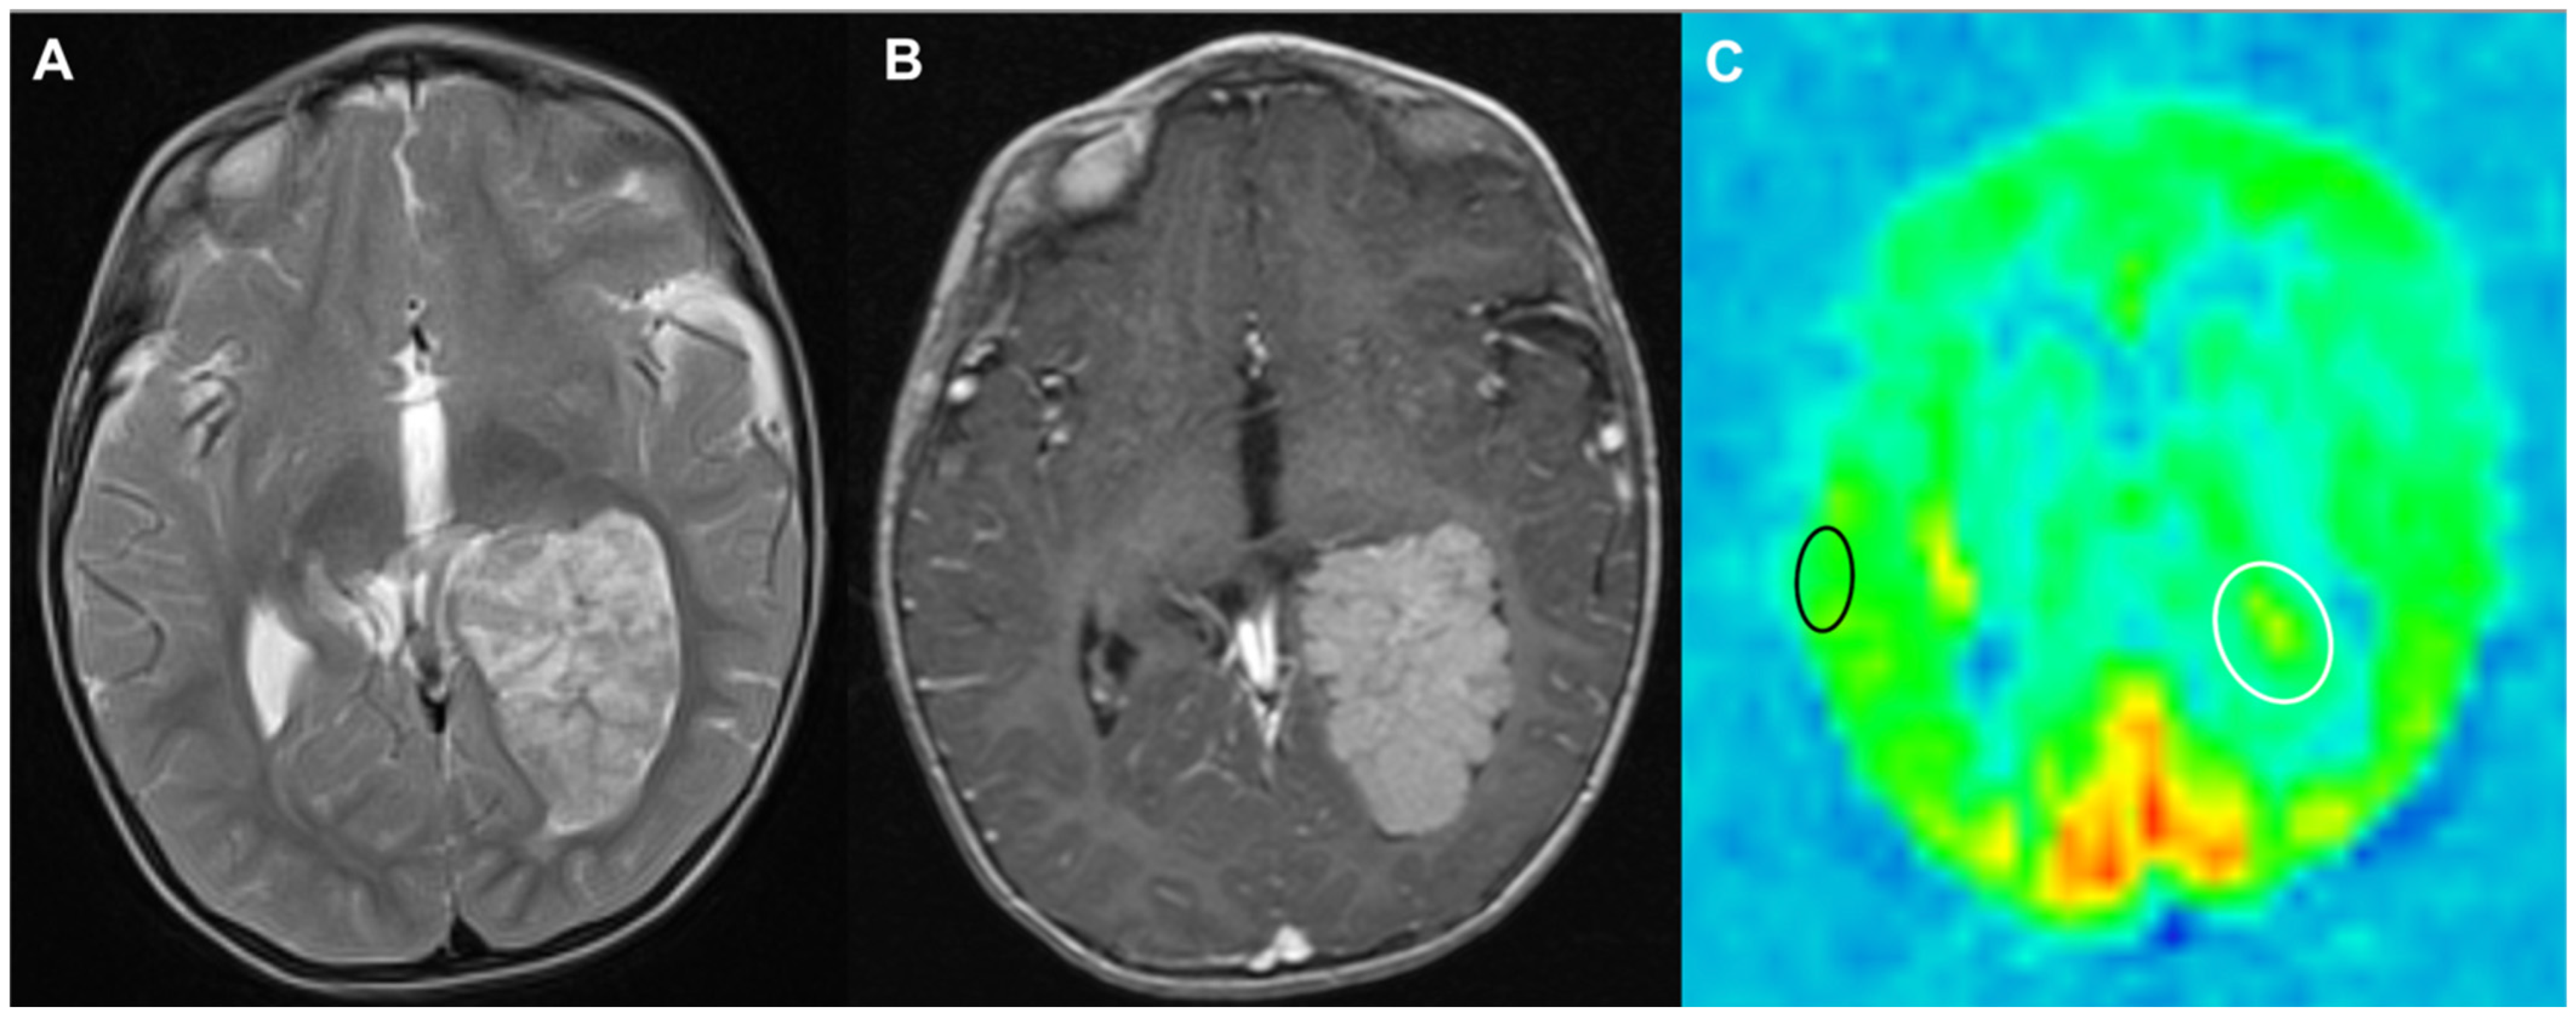

- Troudi, A.; Tensaouti, F.; Cabarrou, B.; Arribarat, G.; Pollidoro, L.; Péran, P.; Sevely, A.; Roques, M.; Chaix, Y.; Bertozzi, A.I.; et al. A Prospective Study of Arterial Spin Labelling in Paediatric Posterior Fossa Tumour Survivors: A Correlation with Neurocognitive Impairment. Clin. Oncol. (R Coll. Radiol.) 2024, 36, 56–64. [Google Scholar] [CrossRef] [PubMed]